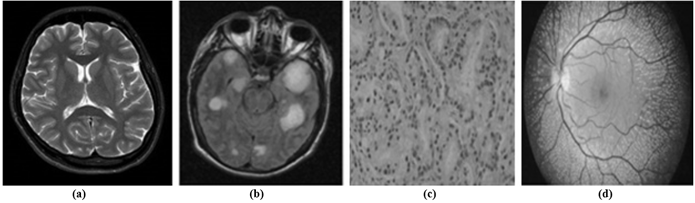

Figure 4. Sample set of images.

A. Subjective Assessment

A set of sample images as shown in Figure 4 are chosen for qualitative analysis of the proposed algorithm. Figure 5 demonstrates the comparative view of a sample image (Figure 4(d)) processed by various transformation techniques such as curvelet transform (CVT), dual-tree complex wavelet transform (DTCWT), multiresolution Singular Value Decomposition (MSVD), convolutional sparsity-based morphological component analysis (CS-MCA), non-subsampled Shearlet Transform (NSST), and the proposed method. By comparing the listed methods, our proposed algorithm demonstrates a suitable brightness with a more appropriate structure. Figure 5 shows that the result of DT-CWT and MSVD methods have low contrast, whereas NSST-based fusion produces over-enhanced images. Though the method CSMCA provides a better structure, it fails to enhance the contrast. The proposed method not only enhances the contrast but also limits the brightness.